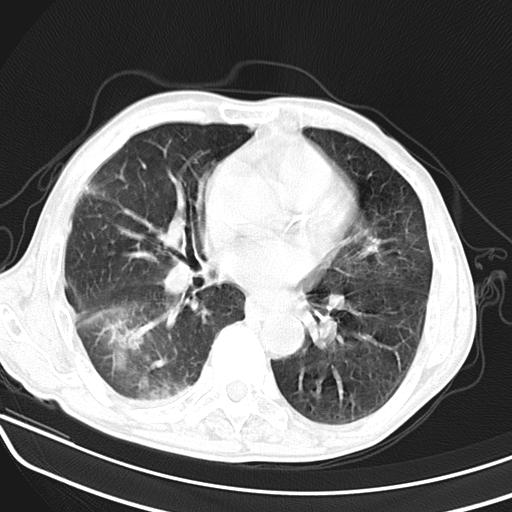

抗炎治疗10天后复查

抗炎治疗10天后复查:右上肺模糊阴影明显减少。